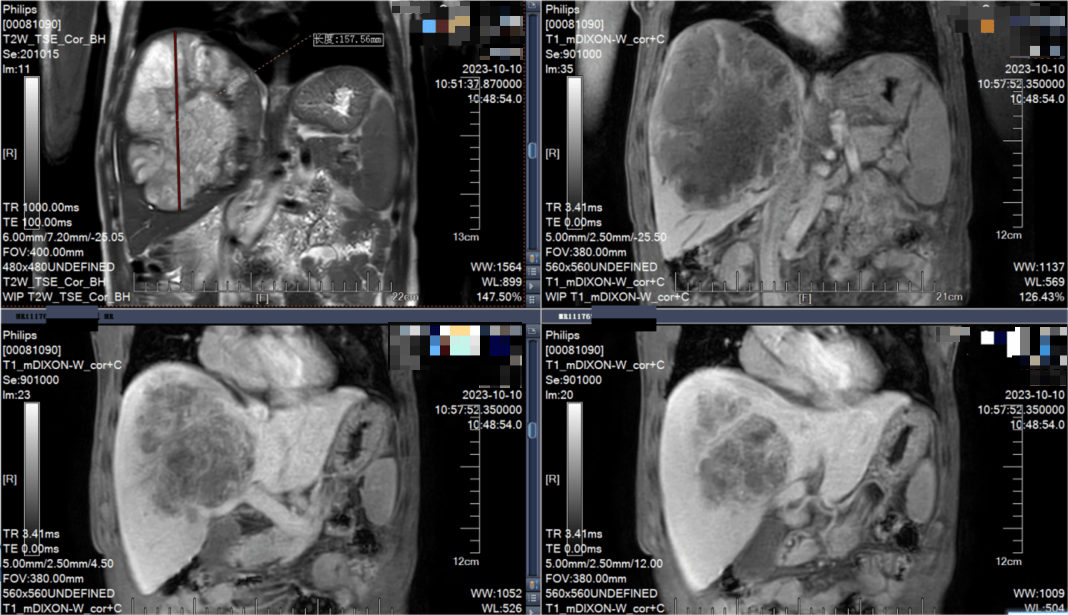

治疗于2023年9月8日正式启动。第一个周期结束后,奇迹的曙光便已显现:王先生的腹胀症状明显减轻,肿瘤缩小至15.76 cm,肿瘤标志物甲胎蛋白(AFP)也从入院时的>1210 ng/ml大幅降至176 ng/ml。这初步证明了联合策略的有效性,为王先生和王效谦教授团队注入了强大的信心。

2023年10月10日 MRI